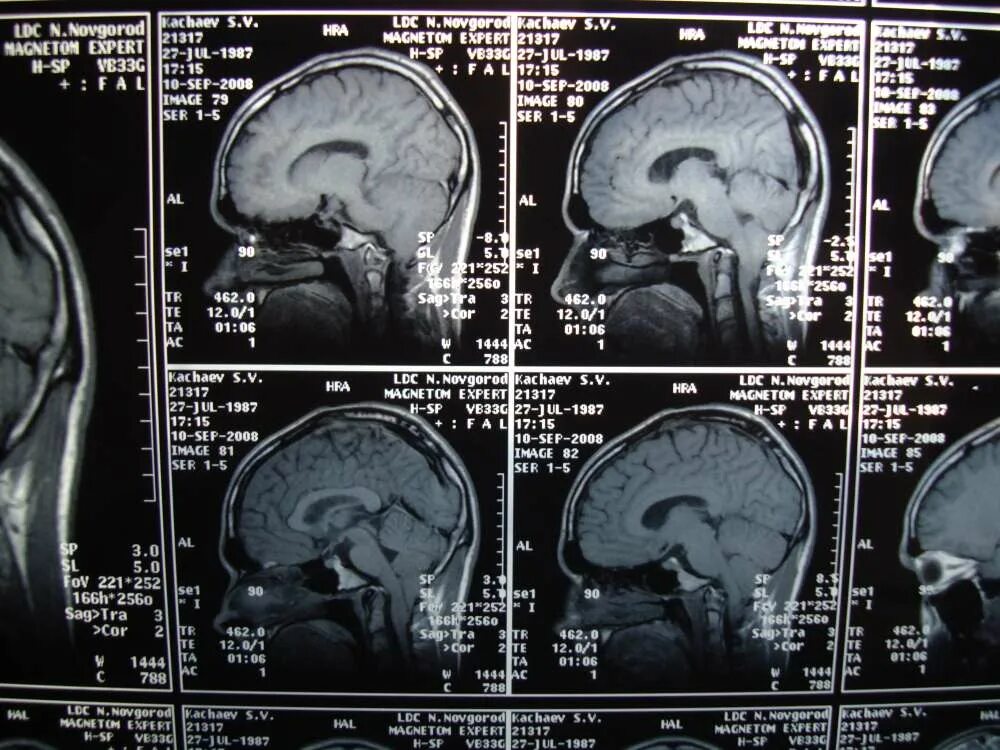

Сколько раз делать мрт головы